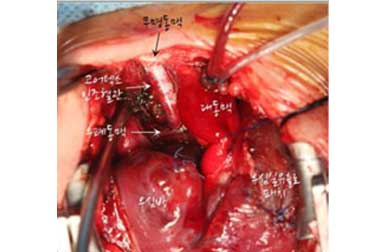

(1) 상대정맥-폐동맥 단락술 후의 모습

상대정맥-폐동맥 단락술 후의 모습